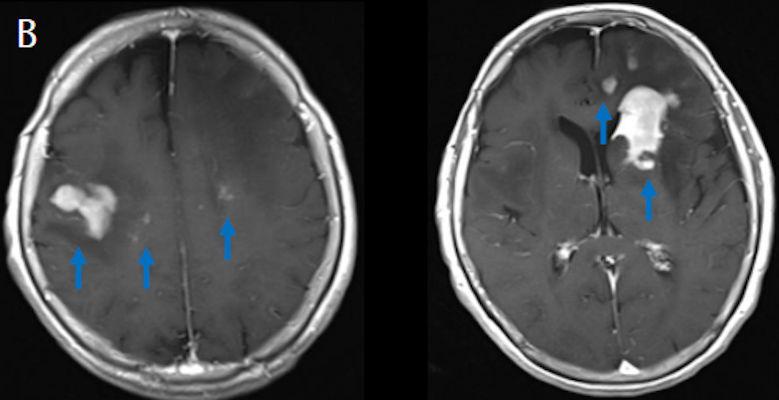

- (B) Aksiyel postkontrast T1A görüntülerde büyüğü sol frontalde kontrastlanma gösteren multipl kitle lezyonları (oklar) izlenmektedir.

- Genellikle supratentoriyal alanda, bazal ganglion, periventriküler beyaz cevher, orta hat ve korpus kallozum vb. yerleşme eğiliminde tek veya multipl kitleler şeklinde görülür.

- Kitleler çoğunlukla solid ve homojendir.